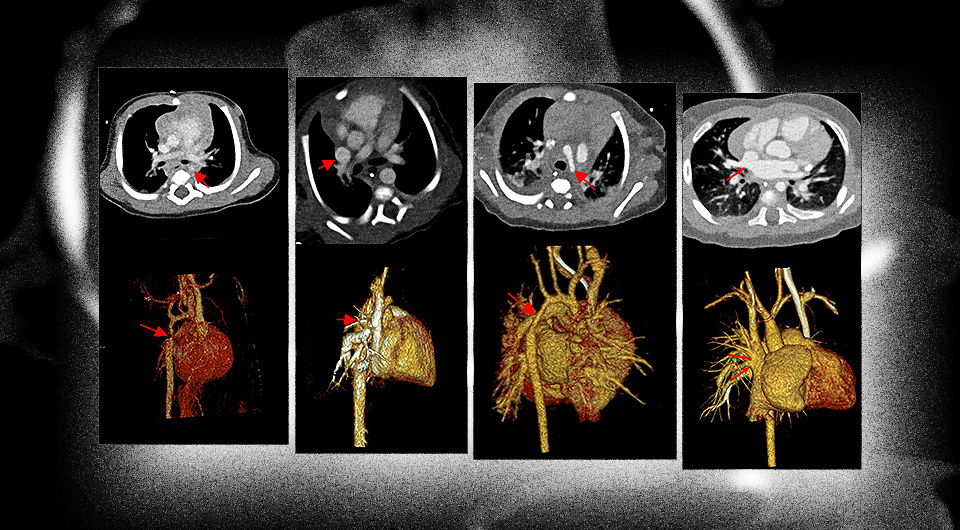

Компьютерная томография (КТ) с подсчетом фотонов показала более четкие и контрастные изображения у детей с врожденными пороками сердца, нежели КТ с двумя источниками излучения. Немецкие радиологи в статье для журнала Radiology, отмечают, что оба метода имеют схожую дозу облучения.